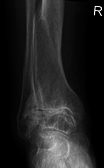

Diagnosis is made with reasonable certainty based on history and clinical examination.[42][43] X-rays may confirm the diagnosis. The typical changes seen on X-ray include: joint space narrowing, subchondral sclerosis (increased bone formation around the joint), subchondral cyst formation, and osteophytes.[44] Plain films may not correlate with the findings on physical examination or with the degree of pain.[45] Usually other imaging techniques are not necessary to clinically diagnose OA.

Related pathologies whose names may be confused with OA include pseudo-arthrosis. This is derived from the Greek roots pseudo-, meaning "false", and arthr-, meaning "joint", together with the ending -osis used for disorders. Radiographic diagnosis results in diagnosis of a fracture within a joint, which is not to be confused with OA which is a degenerative pathology affecting a high incidence of distal phalangeal joints of female patients. A polished ivory-like appearance may also develop on the bones of the affected joints, reflecting a change called eburnation.[48]

Severe osteoarthritis and osteopenia of the carpal joint and 1st carpometacarpel joint.